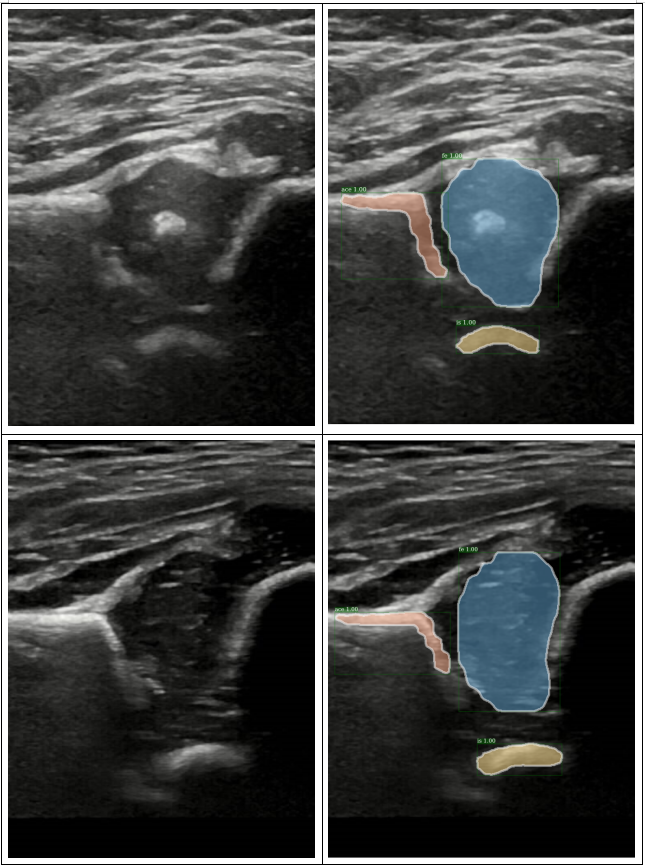

这个指标真是厉害了啊,AP50和AP75竟然都是1。。。看一下结果吧,,

看一下效果啦: